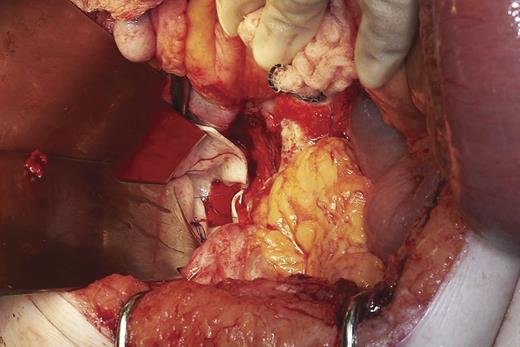

At operation, small bowel obstruction was found with volvulus of a loop of ileum around an adhesion at the neck of the perineal hernia (Fig. 2). Around 80 cm of gangrenous mid-ileum was resected and a primary end-to-end anastamosis performed. After thorough washout of the abdomen and pelvis, the wide pelvic floor defect was bridged with Strattice™ Tissue Matrix, secured in place with 2.0 prolene sutures (Fig. 3). An omental pedicle graft was used to cover the mesh and fill the pelvis. One abdominal tube drain and two perineal suction drains were inserted and removed over the course of the next 7 days.

Bridging of perineal defect with Strattice™ Tissue Matrix before covering with omentum.